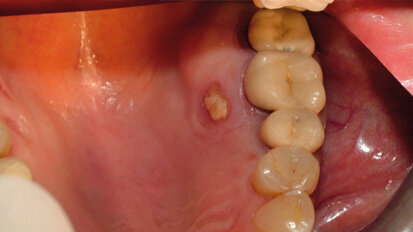

MRONJ del palato: case report

La BRONJ (Bisphosphonate-Related OsteoNecrosis of the Jaws) è definita come un’area di osso esposto nella regione maxillo-facciale che non ...